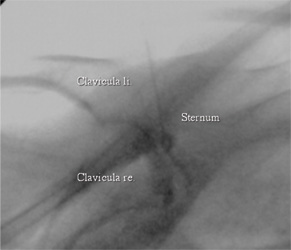

"Testgelenke" dieser Erkrankung sind die artikulären und ligamentären Verbindungen zwischen den Schlüsselbeinen, dem Brustbein und den ersten Rippen. Hier manifestiert sich eine rheumatische Entzündung mit Kombinationen aus arthritisch-destruierenden und enthesiosynovitisch osteoproliferierenden Veränderungen, welche in eine Weichgewebeossifikation und Hyperostose einmünden kann. Die früharthritischen Veränderungen werden sowohl mit der Szintigraphie als auch mit der MRT diagnostiziert, die ankylosierten und ossifizierten Spätfolgen lassen sich mit der CT am besten darstellen. Mit zunehmenden Verknöcherungen sind klinisch zunehmende Beeinträchtigungen der Beweglichkeit im Schultergürtel verbunden.

Die Sternoclaviculargelenke lassen sich unter Monitoring mit der CT und der Durchleuchtung sicher und komplikationslos punktieren. Vor der intraartikulären Corticoninjektion wird eine Arthrographie mit 1 ml Kontrastmittel durchgeführt, welche die Sicherheit einer genauen Nadelposition erhöht (unten).